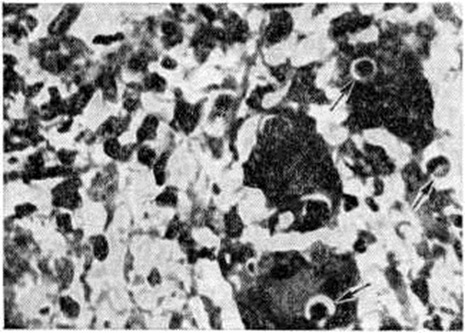

При первой — в центре поражённого участка лёгкого обнаруживают лейкоциты, окружённые эпителиоидными, плазматическими и единичными гигантскими клетками; для второй стадии характерно разрастание грануляционной ткани в очагах поражения; в третьей стадии превалируют фиброзные изменения. Клинически кандидоз лёгких может протекать в лёгкой, средней тяжести и тяжёлой формах; тяжесть течения зависит от распространённости деструктивных изменений в лёгких. В начальной стадии болезни и в легко протекающих случаях кандидоз лёгких напоминает бронхит (бронхомикоз). Отмечаются сухие и влажные крупно и среднепузырчатые хрипы, мучительный кашель со скудной, сероватого цвета мокротой, иногда имеющей запах дрожжей. Больные жалуются на слабость, недомогание, понижение работоспособности, головную боль. Температура тела, как правило, нормальная. В ряде случаев заболевание начинается внезапно с подъёма температуры до высоких цифр. Затем появляется кашель, обычно сухой, «царапающий», сопровождающийся болями в груди. Рентгенологически при этом определяется небольшое усиление лёгочного рисунка. В поздние стадии и при тяжёлом течении кандидоз лёгких проявляется очаговой или лобарной пневмонией (смотри полный свод знаний). Общее состояние больных обычно тяжёлое, наблюдается высокая или умеренно повышенная температура, почти всегда постоянный кашель, сопровождающийся отделением обильной мокроты, кровохарканьем и часто болями в груди. В затяжных случаях кандидапневмония осложняется плевритом (смотри полный свод знаний) с соответствующей симптоматикой. Рентгенография при затяжном течении процесса выявляет неясную пятнистость, небольшие бронхопновмонические очаги и ателектазы, более крупные очаги локализуются, как правило, в нижних долях лёгких. Нередко при кандидапневмонии рентгенологически определяются милиарные затемнения («снеговые хлопья»), тяжистые тени от очагов затемнения к бронхолёгочным (корневым) лимфатических, узлам, нередки случаи распада инфильтратов с образованием единичных крупных или множественных мелких каверн. В этом случае рентгенологическое картина кандидапневмонии напоминает кавернозный туберкулёз лёгких, однако для неё характерно быстрое возникновение тонкостенных полостей, увеличивающихся в размерах и сравнительно быстрый их регресс вплоть до полного исчезновения йод влиянием противомикотической терапии. Рентгенологические данные о распаде лёгочной ткани, связанном с действием самого грибка кандида, должны всегда подкрепляться исследованием всего «микробного пейзажа», так как распад может быть обусловлен другими микроорганизмами, ассоциирующимися с грибком кандида. Изменение картины крови при кандидозе может отсутствовать, в тяжёлых случаях наблюдаются лейкопения, базофилия, эозинофилия, нейтрофилез, лимфопения с моноцитозом, ускорение РОЭ. При вторичном кандидозе лёгких, несмотря на терапию основного заболевания, изменения в лёгких прогрессируют, температура тела становится гектической, возникают озноб, ночные поты, общее состояние больных резко ухудшается. Для постановки диагноза кандидоза недостаточно одних клинические, симптомов. Необходимы микроскопические, культуральные, серологический исследования. При кандидозе лёгких материалом для исследования могут быть мокрота, бронхиальный секрет, аспирированный через бронхоскоп. Лечение кандидоза лёгких проводят с помощью амфоглюкамина, микогептина, нистатина, при тяжёлом течении применяют натриевую соль леворина и амфоглюкамина в виде ингаляций. Прогноз при своевременной терапии благоприятный, однако при тяжёлом течении он зависит от тяжести сопутствующей патологии. Криптококкоз лёгких — заболевание лёгких, вызываемое грибком Cryptococcus neoformans (смотри полный свод знаний Криптококкоз). Верхние дыхательные пути и лёгкие являются воротами проникновения криптококков, однако поражение лёгких при криптококкозе наблюдается реже, чем поражение головного мозга и его оболочек, кожи и слизистых оболочек, а первичный лёгочный криптококкоз — редкость. Вторичный криптококкоз лёгких встречается в бессимптомной, субклинической, острой, подострой (наиболее часто) и хронический формах. Изменения в лёгких при криптококкозе носят очаговый характер. Очаги могут быть одиночными или множественными с вовлечением в патологический процесс одной или нескольких долей лёгкого и представляют собой желатинозные уплотнённые участки диаметром до 7—10 сантиметров, не подвергающиеся казеозному некрозу, склонные к фиброзированию. При острой криптококкозной пневмонии грибки, заполняющие альвеолы, имеют округлую форму с чёткими контурами, диаметром от 5 до 20 микрометров с темным центром и широким светлым ободком. При хронический течении процесса по периферии очагов поражения развивается грануляционная ткань. Такие ограниченные, стационарные очаги называются криптококкомами (рисунок 1), по старой классификации — торулемами. В некоторых случаях острый криптококкоз лёгких начинается с озноба, повышения температуры тела до 38—40°, болей в грудной клетке. Чаще заболевание начинается исподволь, причём в начальные стадии — без выраженных клинические, проявлений; может возникнуть сухой кашель, у ряда больных появляется скудная слизистая мокрота, иногда с прожилками крови. Умеренные клинические, проявления сопровождаются выраженными рентгено л. изменениями в виде плотных массивных теней, сходных с туберкуломами. Каверны образуются редко. На рентгенограмме также определяются криптококкомы — одиночные псевдо-опухолевые очаги затемнения умеренной плотности, обычно без расширения тени корней лёгких.

Диагноз криптококкоза при цитологический исследовании мокроты и гистологический исследовании биоптатов ткани лёгкого становится убедительным после постановки PAS-реакции (смотри полный свод знаний ШИК-реакция) и применения других методик, позволяющих выявить располагающуюся вокруг грибка желатинозную капсулу, богатую глюкозаминогликанами. Этиотропная терапия криптококкоза лёгких предполагает использование амфотерицина В под контролем функции почек. Прогноз при локализованном лёгочном криптококкозе благоприятный. Гематогенная диссеминация процесса сопровождается развитием энцефаломиеломенингита с плохим прогнозом. Известны рецидивы лёгочного криптококкоза. Североамериканский бластомикоз с локализацией первичного патологический процесса в лёгких развивается в результате аэрогенного заражения грибком Blastomyces dermatitidis (смотри полный свод знаний Бластомикозы) и является редкой формой заболевания. Очаги поражения при североамериканском бластомикозе имеют сходство с таковыми при раке или туберкулёзе, так как подвергаются творожистому некрозу или гнойному расплавлению. При гистологический исследовании обнаруживают очаги некроза с разрастанием грануляционной ткани в их окружности, которая содержит гигантские клетки. PAS реакция выявляет Blastomyces dermatitidis среди клеток инфильтрата или в гигантских клетках (рисунок 2). Лёгочная форма североамериканского бластомикоза начинается незаметно и в ранний период может протекать под маской острого респираторного заболевания с небольшим повышением температуры тела, незначительным кашлем, который обычно сопровождается отделением небольшого количества слизистой или слизисто-гнойной мокроты, у некоторых больных наблюдаются боли в грудной клетке. В дальнейшем состояние больных прогрессивно ухудшается, температура тела достигает высоких цифр, сопровождается ночными потами, ознобами, постепенно развиваются слабость, анорексия, истощение. Кашель становится почти постоянным и мучительным, мокрота — обильной и гнойной, часто с прожилками крови. Физикальное исследование выявляет признаки очаговых изменений в лёгких (локальное притупление перкуторного звука, разнокалиберные хрипы). Иногда очаговые лёгочные поражения остаются изолированными в течение всего своего развития, в некоторых случаях принимают распространённый (диссеминированный) характер. Длительное и прогрессирующее течение болезни может сопровождаться поражением тел позвонков и компрессией спинного мозга. В крови отмечается гипохромная анемия, лейкоцитоз, нейтрофилез, ускорение РОЭ. При рентгенологическое исследовании в начальной стадии болезни обнаруживают увеличение медиастинальных лимфатических, узлов без заметных изменений в ткани лёгкого, в дальнейшем выявляются плотные тени с неправильными контурами, расположенные чаще в области корней лёгких, симулирующие новообразование. Образование каверн нехарактерно, однако иногда они встречаются у лиц пожилого возраста. Лечение осуществляется с помощью амфотерицина В. Прогноз серьёзный, в случае диссеминированного процесса плохой. Паракокцидиоидоз вызывается грибком Paracoccidioides brasiliensis (смотри полный свод знаний Паракокцидиоидоз) и в 80% случаев протекает с первичным поражением лёгких. Паракокцидиоидоз характеризуется хронический прогрессирующим течением и гранулематозным процессом в лёгочной ткани и нередко гнойным воспалением. Общее состояние больных постепенно ухудшается, развиваются астения, анорексия, гектическая лихорадка, ночные поты. Кардинальным симптомом заболевания является кашель со слизистой мокротой, которая со временем становится гнойной с прожилками крови. Как правило, лёгочные поражения сопровождаются повреждением других внутренних органов: желудка, кишечника, печени и так далее, в которых развиваются гранулемы или абсцессы. Рентгенологические исследование выявляет расширение корней лёгких и признаки, сходные с симптомами инфильтративно-кавернозного туберкулёза лёгких (смотри полный свод знаний Туберкулёз органов дыхания). Нередко имеет место сочетание туберкулёза и паракокцидиоидоза. Установление диагноза заболевания возможно только при обнаружении почкующихся дрожжевых клеток в мокроте, соскобах с поверхности грануляций, в выделениях из свищевых ходов. При лечении используется амфотерицин В. Прогноз при своевременной диагностике и терапии благоприятный. Геотрихоз. Возбудитель — грибок рода Geotrichum. Наиболее частой клинические, формой первичного геотрихоза органов дыхания является бронхит. Симптомы интоксикации не выражены. Характерен мучительный кашель, сопровождающийся выделением слизистой или желеобразной мокроты, в которой можно видеть серые комочки мицелия грибка или прожилки крови. При физикальном обследовании больного выявляются грубые свистящие хрипы над областью поражения, преимущественно в базальных сегментах лёгких. Рентгенологические картина характеризуется усилением бронхиального рисунка и наличием нежных пятен затемнения, в основном в нижних долях лёгких. Геотрихоз с преимущественным поражением ткани лёгкого обычно является вторичным. Очаги поражения локализуются в верхних отделах лёгких и могут захватывать целую долю. При гистологический исследовании ткани лёгкого характерных морфологический особенностей, кроме обнаружения грибка, не выявляется. При наличии тонкостенных каверн, являющихся следствием туберкулёзного процесса, осложнившегося геотрихозом, на их стенках находят разросшиеся мицелиальные формы грибка. Заболевание протекает с нерегулярным повышением температуры, одышкой и тахипноэ, тахикардией и явлениями интоксикации. Характерен кашель с выделением светлой мокроты, иногда с прожилками крови. Кровохарканье наблюдается редко. При физикальном исследовании определяется притупление перкуторного звука над очагами поражения, выслушиваются мелкопузырчатые и среднепузырчатые хрипы. Рентгенологически обнаруживают тяжистость лёгочного рисунка, гладко-очерченные плотные тени, в которых могут быть тонкостенные каверны. В крови сегментоядерный лейкоцитоз, ускорение РОЭ. Этиотропное лечение геотрихоза включает амфотерицин В, а также амфоглюкамин в виде ингаляций. Прогноз при своевременном лечении благоприятный. Гистоплазмоз лёгких вызывается Histoplasma capsulatum Darling (смотри полный свод знаний Гистоплазмоз). Первичный гистоплазмоз лёгких в большинстве случаев протекает бессимптомно, но иногда может симулировать грипп и другие острые респираторные заболевания. Вторичный гистоплазмоз лёгких протекает в виде хронический процесса, который периодически обостряется, а иногда переходит в диссеминированный системный гистоплазмоз. Кокцидиоидоз лёгких, вызываемый грибком Coccidioides immitis (смотри полный свод знаний Кокцидиоидоз), чаще встречается в форме первичного и обычно протекает доброкачественно. Морфологически изменения в лёгких при кокцидиоидозе разнообразны: очаги уплотнения лёгочной ткани, обширные студенистые очаги или очаги нагноения, некротический язвенный бронхит, гранулематозные поражения без некроза и очаги обызвествления с некрозом в центре. Реже встречающийся вторичный кокцидиоидоз лёгких имеет сходство с туберкулёзом. При этом наблюдаются казеозная пневмония, абсцессы, в которых обнаруживают сферулы грибка (рисунок 3). Клинические, проявления болезни могут ограничиваться признаками острого респираторного заболевания. Спустя несколько недель наступает выздоровление. У 4—5% инфицированных лиц кокцидиоидоз с поражением лёгких протекает в тяжёлой форме, сопровождается высокой температурой, одышкой, кашлем с гнойной мокротой, иногда кровохарканьем. Наблюдаются резкие колебания температуры в течение суток, сопровождающиеся ознобами и потами. Больные жалуются на головную боль, боль в мышцах, пояснично-крестцовой области. В последующем развиваются анорексия, астения, снижается вес (масса) тела больных. Над лёгкими выслушиваются сухие и влажные хрипы, иногда — шум трения плевры. В течении болезни отмечаются длительные периоды ремиссии. Иногда наблюдается диссеминация возбудителя инфекции и развитие грибкового сепсиса с образованием множественных абсцедирующих инфильтратов в различных органах и тканях.